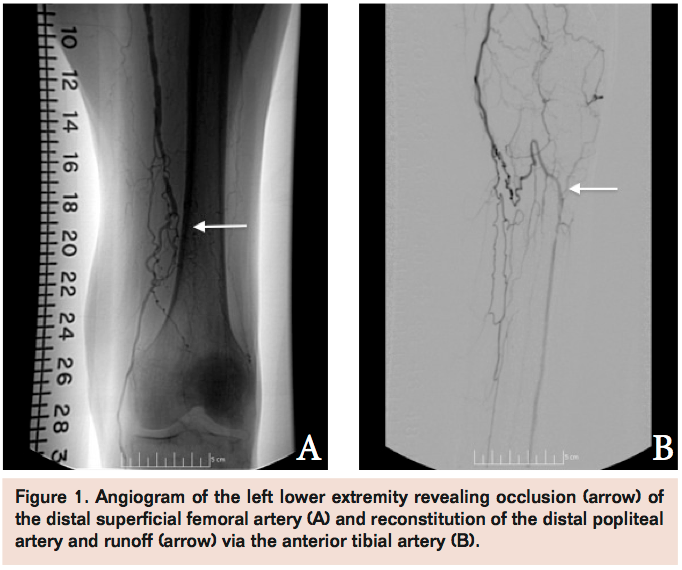

Angiogram of the left common femoral artery with runoff revealed distal left superficial femoral artery occlusion (Figure 1A) with reconstitution of the distal popliteal artery and 2-vessel runoff into the left foot via the anterior tibial and peroneal arteries (Figure 1B). Revascularization of the occlusion was performed using balloon angioplasty and stent placement (Figure 2A) with good angiographic result and runoff (Figure 2B). She had complete resolution of her claudication symptoms, but returned 1 year later with ulceration of the medial aspect of her left foot above the medial malleolus. Repeat angiogram revealed restenosis of the stent (Figure 3A) and re-occlusive disease of the distal popliteal artery stent extending into the anterior tibial artery (Figure 3B) requiring atherectomy and balloon angioplasty for successful revascularization (Figure 4). However, her ulceration progressed despite revascularization, prompting further evaluation of the etiology of her ulcer (Figure 5). A venous Doppler study of the left lower extremity revealed severe reflux of the left greater saphenous vein (Figure 6) with flow above baseline in the proximal, mid, and distal portions of up to 1.7 seconds. An incompetent perforating vein was also noted in the left calf 23 cm from the ankle and measured at 0.33 cm in diameter (Figure 7). She subsequently underwent radiofrequency ablation of the left greater saphenous vein followed by the left calf perforator with complete occlusion by ultrasound (Figure 8).